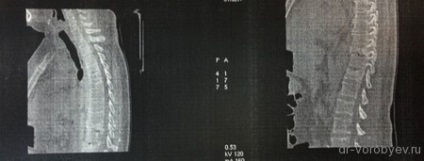

A preoperatív CT-vizsgálat kimutatta, törések a háti csigolyák.

A radiológiai eredmények a műtét után. Valószínűleg jobban meg kellene hajlító hosszú rudat hyphotikus áramkört.